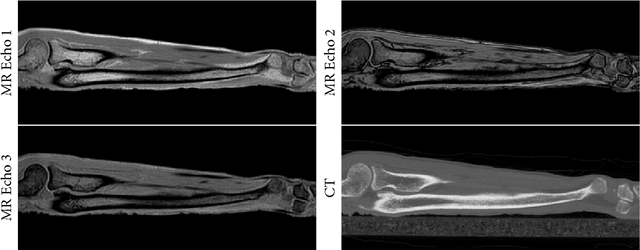

Purpose: To assess the feasibility of deep learning-based high resolution synthetic CT generation from MRI scans of the lower arm for orthopedic applications. Methods: A conditional Generative Adversarial Network was trained to synthesize CT images from multi-echo MR images. A training set of MRI and CT scans of 9 ex vivo lower arms was acquired and the CT images were registered to the MRI images. Three-fold cross-validation was applied to generate independent results for the entire dataset. The synthetic CT images were quantitatively evaluated with the mean absolute error metric, and Dice similarity and surface to surface distance on cortical bone segmentations. Results: The mean absolute error was 63.5 HU on the overall tissue volume and 144.2 HU on the cortical bone. The mean Dice similarity of the cortical bone segmentations was 0.86. The average surface to surface distance between bone on real and synthetic CT was 0.48 mm. Qualitatively, the synthetic CT images corresponded well with the real CT scans and partially maintained high resolution structures in the trabecular bone. The bone segmentations on synthetic CT images showed some false positives on tendons, but the general shape of the bone was accurately reconstructed. Conclusions: This study demonstrates that high quality synthetic CT can be generated from MRI scans of the lower arm. The good correspondence of the bone segmentations demonstrates that synthetic CT could be competitive with real CT in applications that depend on such segmentations, such as planning of orthopedic surgery and 3D printing.